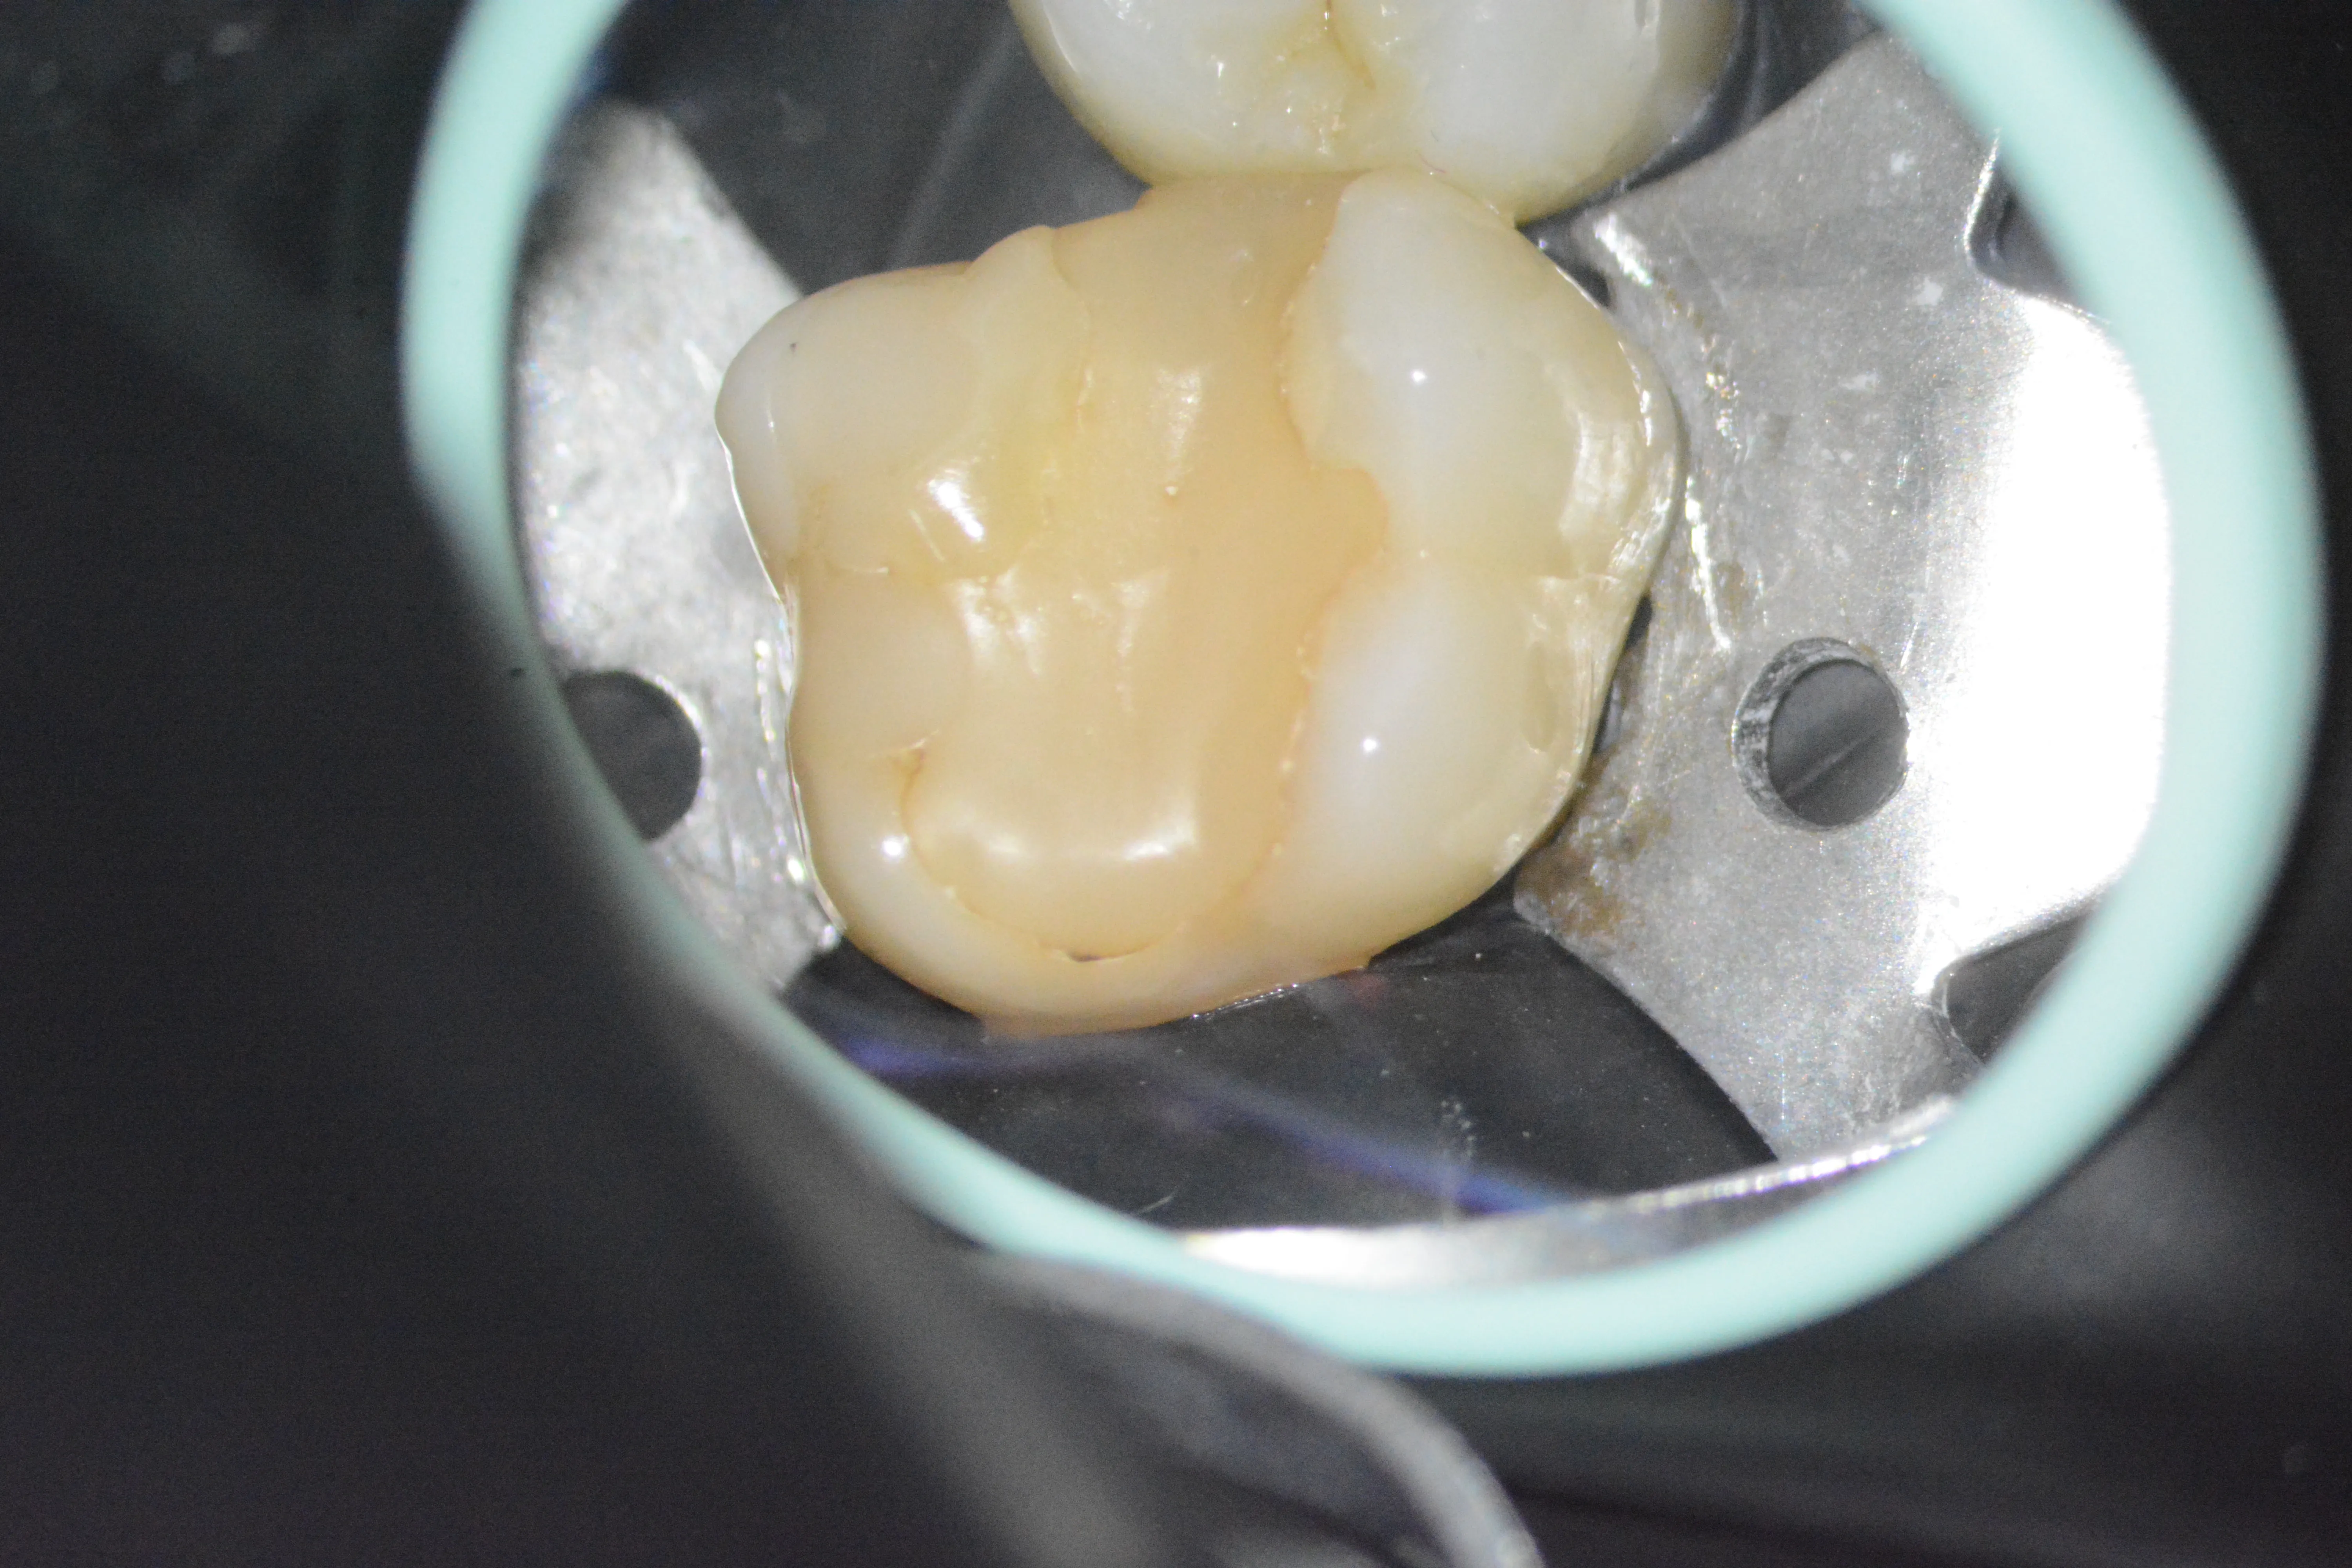

12 – Aplicarea sistemului de matrici